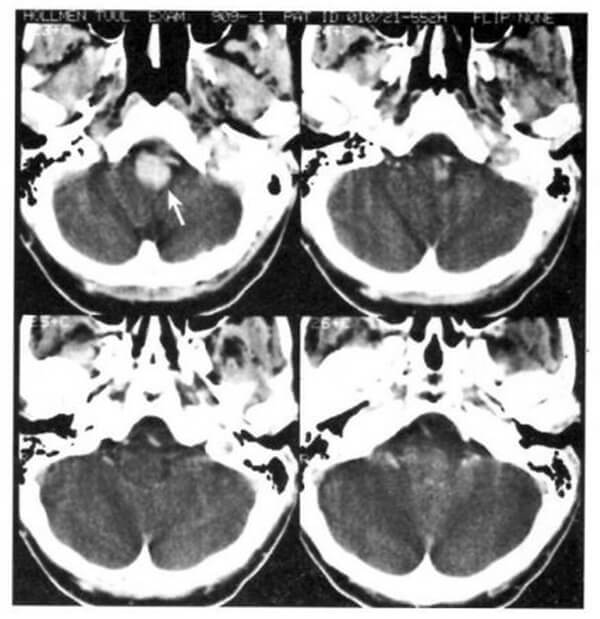

1.3. U nguyên bào tủy (Hình 1.58)

Dấu hiệu XQCLĐT:

– Điển hình ở thùy nhộng tiểu não, thường có mật độ hơi cao hơn nhu mô tiểu não bình thường. Bắt chất cản quang rõ trừ khi hoại tử.

– Não úng thủy do tắc nghẽn não thất 4.

– Di căn theo khoảng dưới nhện.

Chú giải:

– U hố sau thường gặp ở trẻ em. U ngoại bì thần kinh nguyên phát sinh ra từ chất mầm của trần não thất 4. 50% xảy ra trước 10 tuổi.

– Saccom tiểu não là một u đặc nhiều thùy, lớn được xem là u nguyên bào tủy ngoại vi.

Hình 1.58. U nguyên bào tủy của thùy nhộng tiểu não ở trẻ 2 tuổi. Cắt lớp cách sau 10 tháng. Trước tiêm (a), dấu hiệu mơ hồ (mũi tên). Sau tiêm (b), một phần u bắt chất cản quang mạnh.